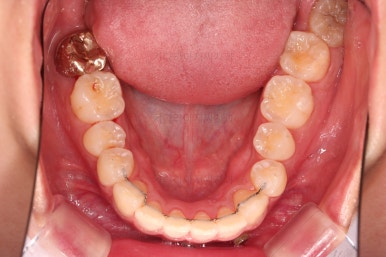

4. 마무리

다시 틀어지지 말라고, 철사형 유지장치를 부착했고요.

과개교합이 재발되지 말라고 특수한 형태의 유지장치를 추가로 만들어드렸습니다.

부분교정치고는 비교적 긴 기간이었고(13개월), 중간에 타지역으로 발령나는 바람에 내원도 힘드셨지만, 약속도 매우 잘 지켜주셨고 협조도 좋아 잘 마무리 되었습니다.

부산앞니부분교정 전후 비교해 볼게요.

배열, 과개교합, 튀어나온 앞니, 심지어 약간의 입매개선까지.

난이도 높은 부분교정이 잘 마무리 되었습니다.